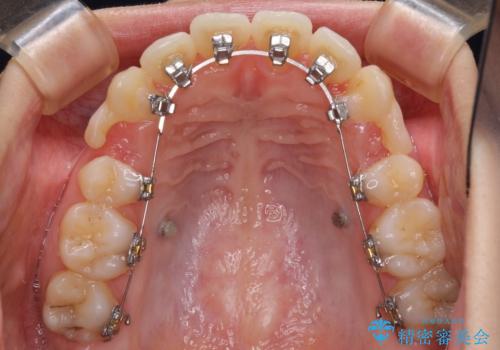

- 矯正装置

- ハーフリンガル

目立たない装置が希望であったため、上顎が裏側装置である、ハーフリンガル装置を選択されました。